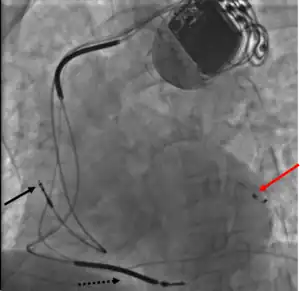

A terapia de ressincronização cardíaca (ing. Cardiac Resynchronization Therapy, CRT) - é um tratamento da , insuficiência cardíaca congestiva, que envolve o implante de eletrodos no coração para "cardioestimular" de forma sincrônica ambos ventrículos. Em alguns casos, também é possível estimular apenas o ventrículo esquerdo.

Na insuficiência cardíaca avançada, esse implante é utilizado para tratar um distúrbio da estimulação do ventrículo esquerdo (como dessincronia na contração). No eletrocardiograma, este fenômeno é acompanhado por ampliação do complexo QRS, sendo a origem de tal modificação, em muitos casos, o bloqueio do ramo esquerdo do feixe.

Outros nomes: estimulação de ressincronização, a estimulação de dupla câmara A assincronia sistólica entre os ventrículos esquerdo e o direito leva à contração antecipada do septo em relação à parede lateral do ventrículo esquerdo, o que dificulta o enchimento durante a diástole. Sendo assim, tal assincronia diminui o volume de ejeção sistólico.